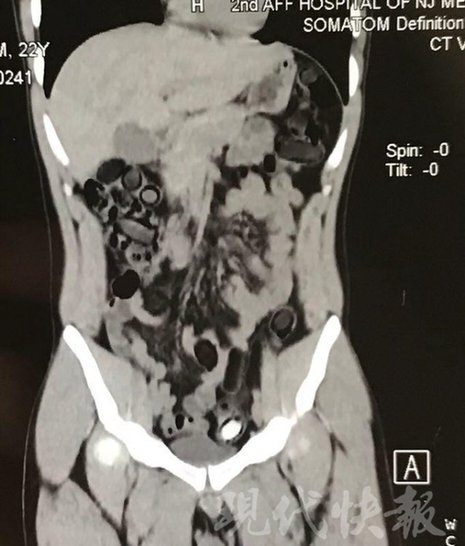

小伙體內(nèi)藏毒300余克 CT掃描圖密密麻麻

由于毒品在體內(nèi)一旦泄露有可能致命,警方第一時間將阿永帶到醫(yī)院進(jìn)行檢查。CT 掃描的結(jié)果顯示,阿永體內(nèi)布滿了密密麻麻的白色圓柱狀固體,就像一粒粒的蠶蛹。在南京市公安局鼓樓分局二板橋派出所,阿永分四次排出了毒品,毛重369.99克。經(jīng)訊問,阿永交代了自己全部的犯罪事實(shí)。目前,阿永已被刑事拘留。